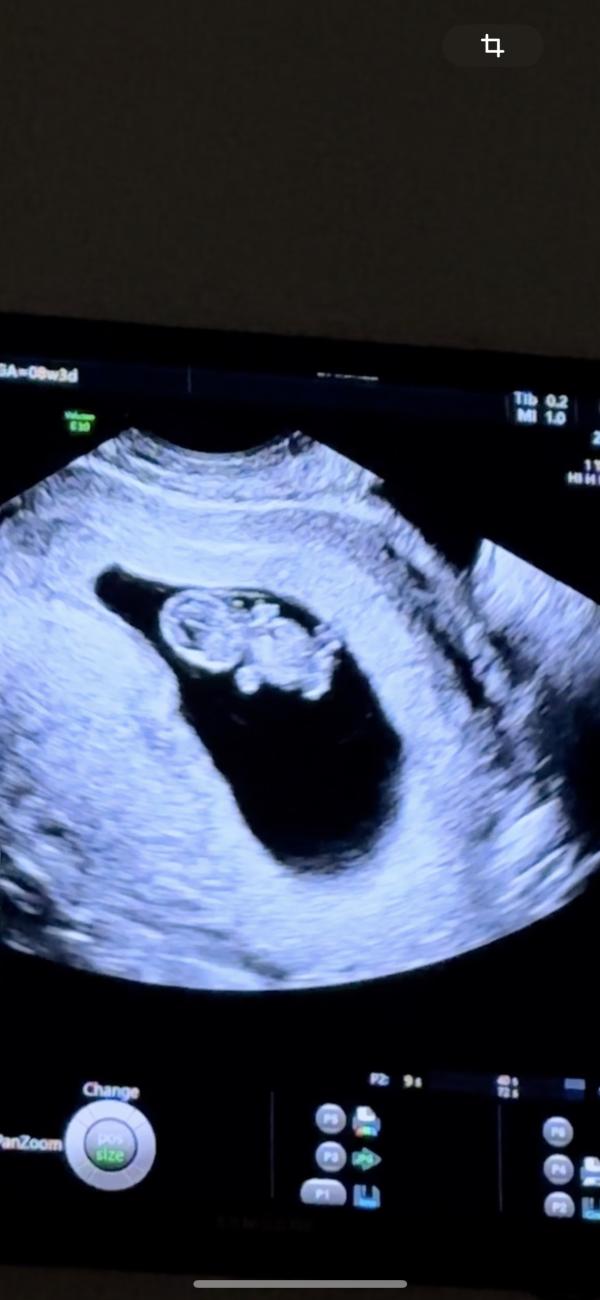

Вчера ходили на узи смотреть малыша, там уже виден человечек и он даже шевелится😍😍😍Наконец то ко мне пришло осознание, что я беременна🤩Эта беременность совсем другая, ни токсикоза, ни живота пока нет. Единственное, все вокруг ждут мальчика, а мне кажется, что снова девочка😂

@mom_of_twins2016, прикольно просто) такой уже человечек ❤️ Я была на узи 9нед и 4 дня, но там совсем не так как у вас.

@27moldir, возможно от аппарата зависит) я тоже была удивлена, что он уже такой😄